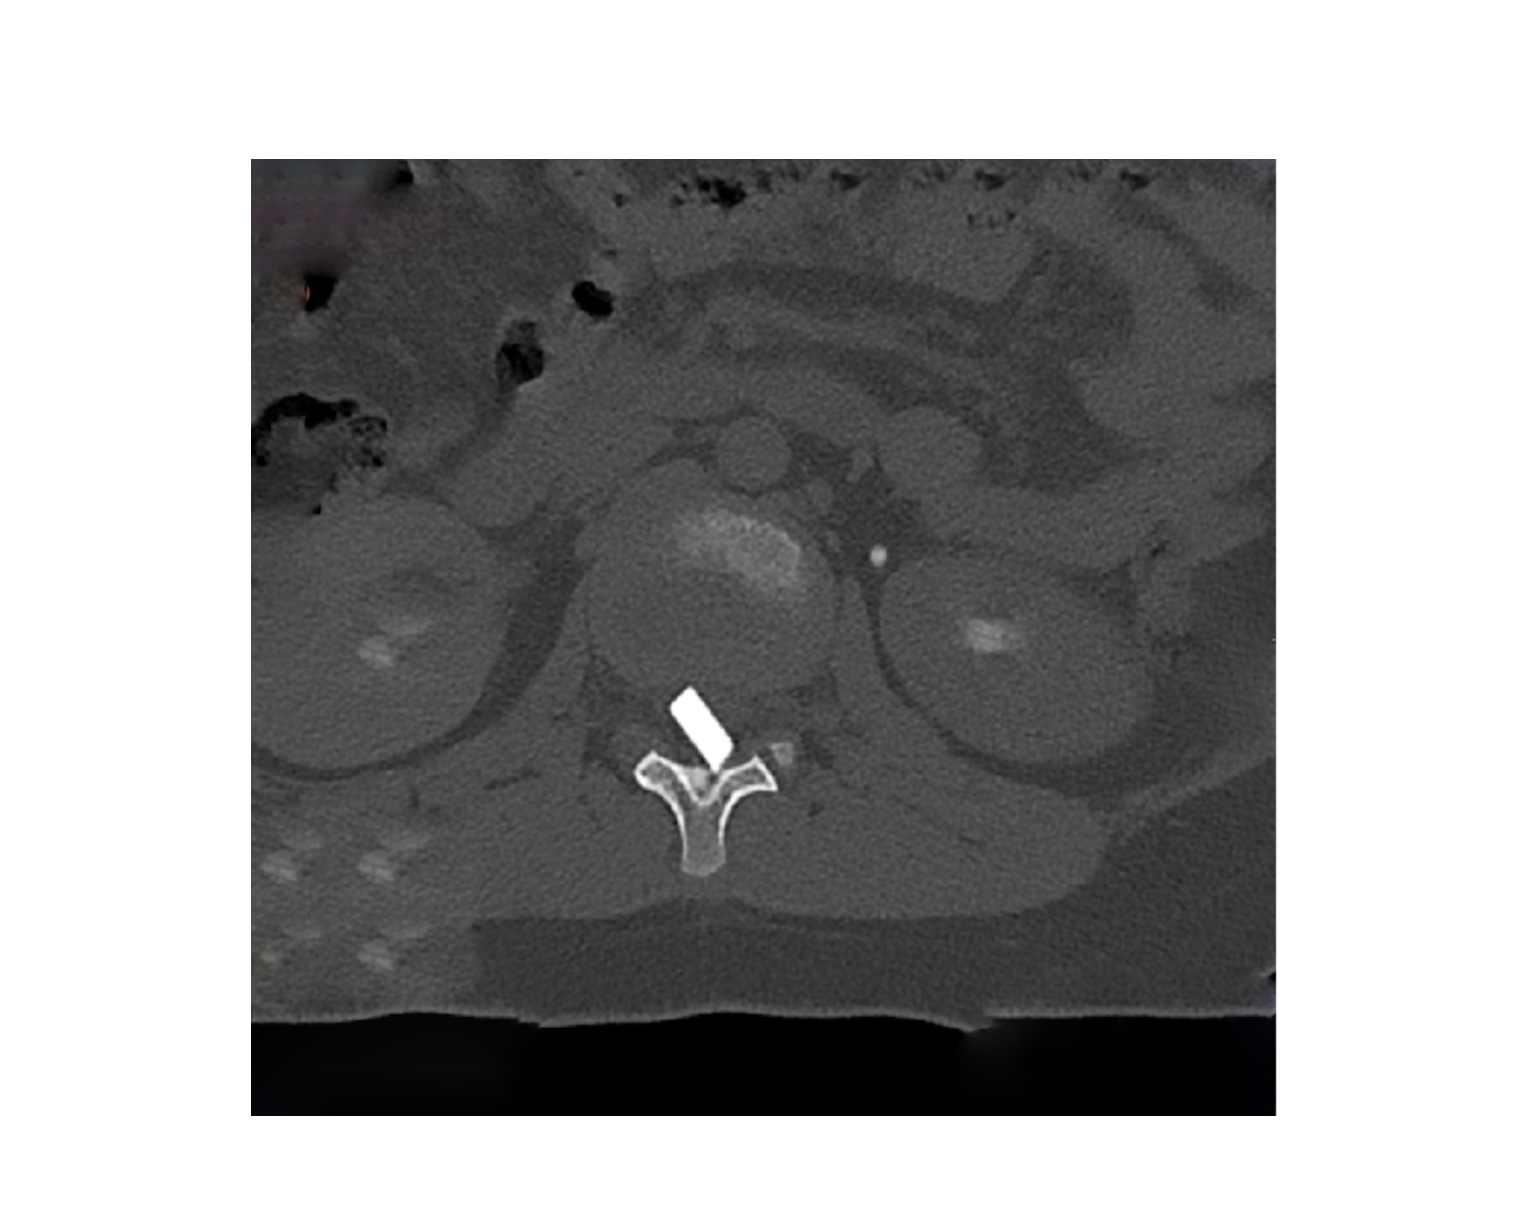

Οι μαγνητικές και αξονικές τομογραφίες πραγματοποιήθηκαν άμεσα, επιβεβαιώνοντας τις αρχικές υποψίες: δύο μεγάλα κομμάτια γυαλιού είχαν ενσφηνωθεί στη σπονδυλική στήλη, εισχωρώντας εντός του σπονδυλικού σωλήνα σχίζοντας την ιππουρίδα και την μήνιγγα που την περιβάλλει.

Ακολούθησε άμεση εισαγωγή του παιδιού στο χειρουργείο, όπου με πολύ προσεκτικούς χειρισμούς και τη χρήση προηγμένου εξοπλισμού, όπως το σύστημα χειρουργικής πλοήγησης, πραγματοποιήθηκε επιτυχής αφαίρεση όλων των κομματιών γυαλιού μετά από ένα πολύωρο και απαιτητικό χειρουργείο.